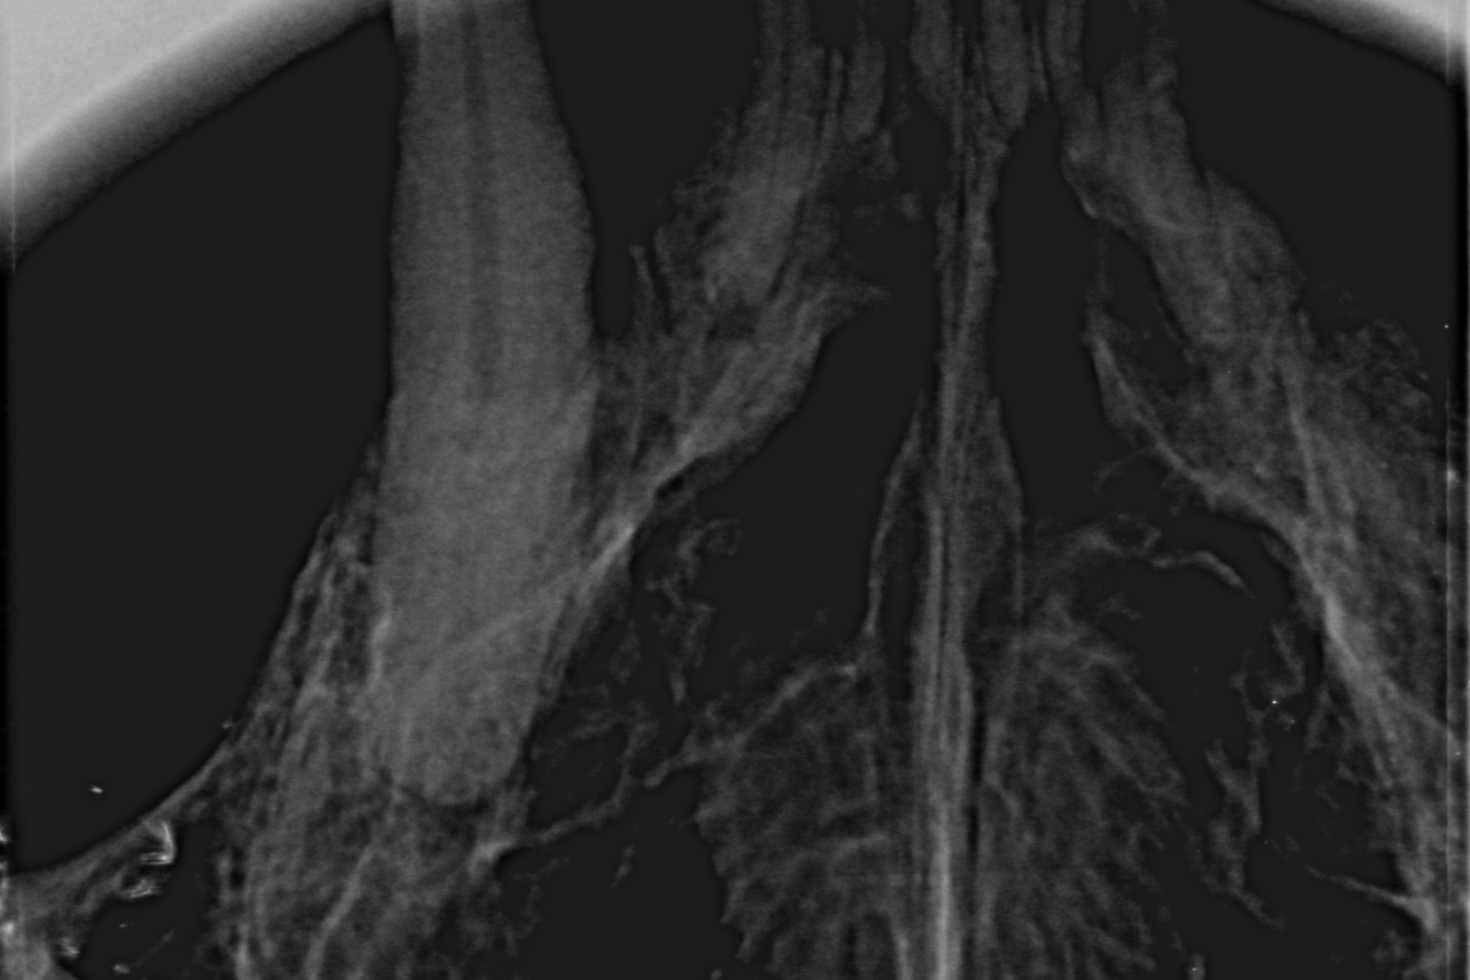

Auf diesen Bildern sehe ich etwas mehr als auf den herkömmlichen chemisch entwickelten Aufnahmen. Die Aufnahmen können vergrößert oder gefiltert werden. Sie lassen sich unkompliziert speichern und verschicken. Der Kunde kann eine Datei mitnehmen; der fachliche Austausch unter Tierärzten wird schneller.

Aber der Clou ist: Die Speicherfolien sind so klein, daß ich damit einen entscheidenden technologischen Vorteil gegenüber meiner alten Technik habe. Ich kann überlagerungsfrei jeden Zahn einzeln darstellen. Ich kann auch Pfötchen und Flügel röntgen, ohne gleich den ganz großen Apparatismus anzuwerfen.

Ein paar Beispielaufnahmen

aus unserer Röntgenpraxis